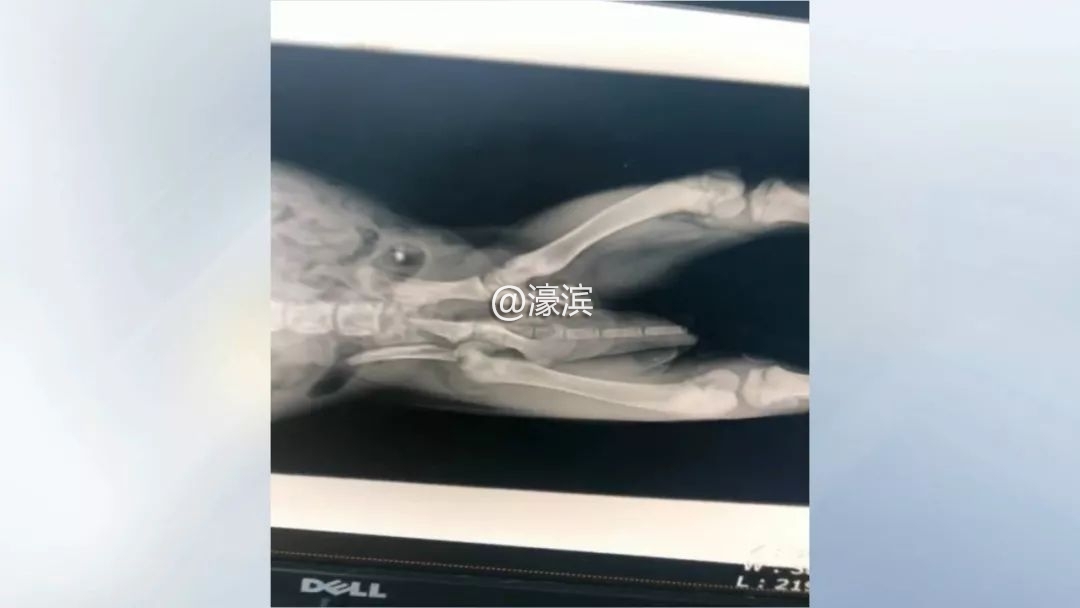

宠物医院负责人 袁嘉:送过来之后检查发现整个盆骨粉碎性骨折,再加上股骨头的断裂,再加上腹腔和胸腔的大面积的内出血。

确诊伤情后,兽医们立即为小狗进行手术。遗憾的是,由于受伤太重,经过大家三个小时的努力,最终还是没能抢救过来。

宠物医院负责人 袁嘉:当我们剖腹探查之后发现,它是肾脏破裂,这就没有办法了,我们大家都已经尽力了。